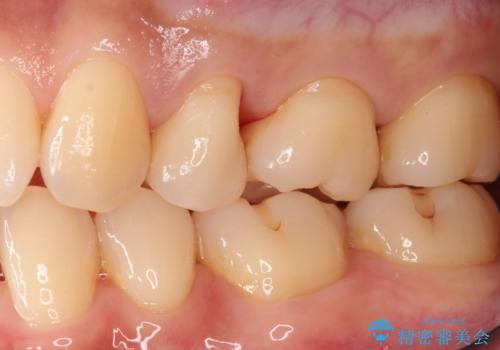

適合の良いセラミックインレー

- 定期検診して虫歯を認めたため、セラミックインレーにて修復治療を行なっております。

e-max プレスインレーにて修復治療を行っているため適合性及び審美性の高い治療を行うことができます